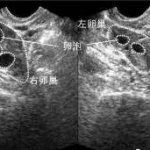

北京做试管婴儿好吗?